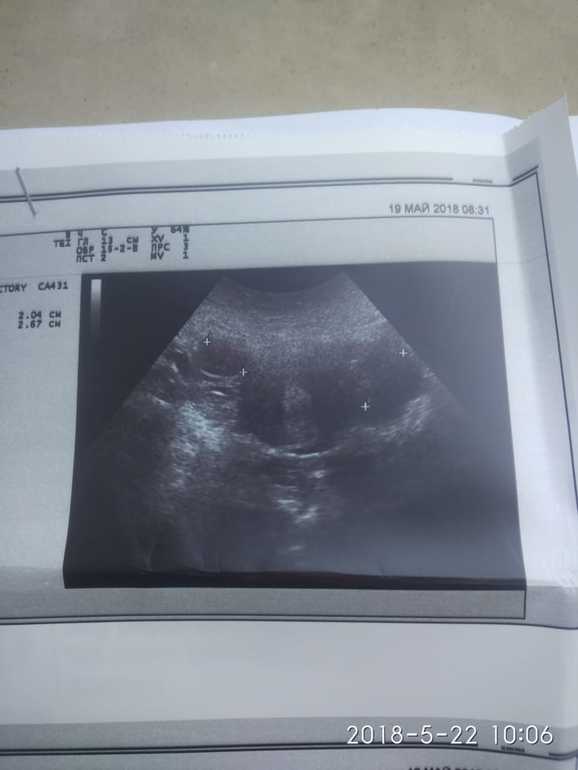

Добрый день! проходите УЗИ после менструации, одно из образований следует дифференцировать с эндометриоидной кистой. Очень размытое изображение. В таких случаях исключают также параовариальные образования.

Если я правильно понимаю, то жт должно быть одно, а тут три... Скорее всего фолликулы, а что в заключении УЗИ?